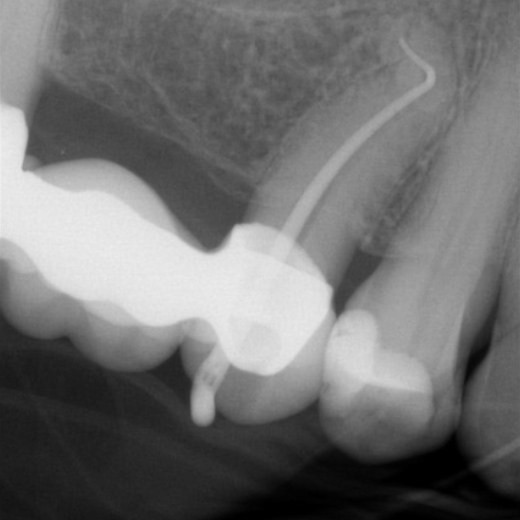

Fallbeispiel: Molarenrevision mit Seitenkanal

Werden im Rahmen einer Wurzelkanalbehandlung nicht alle Bereiche innerhalb des Wurzelkanalsystems ausreichend gereinigt, kann es zu persistierenden Infektionen kommen. In diesem Fall war die persistierende Infektion auf einen feinen Seitenkanal zurückzuführen – mit einer Revisionsbehandlung und gründlicher Reinigung des Wurzelkanalsystems können auch solche persistierenden Infektionen erfolgreich behandelt werden!